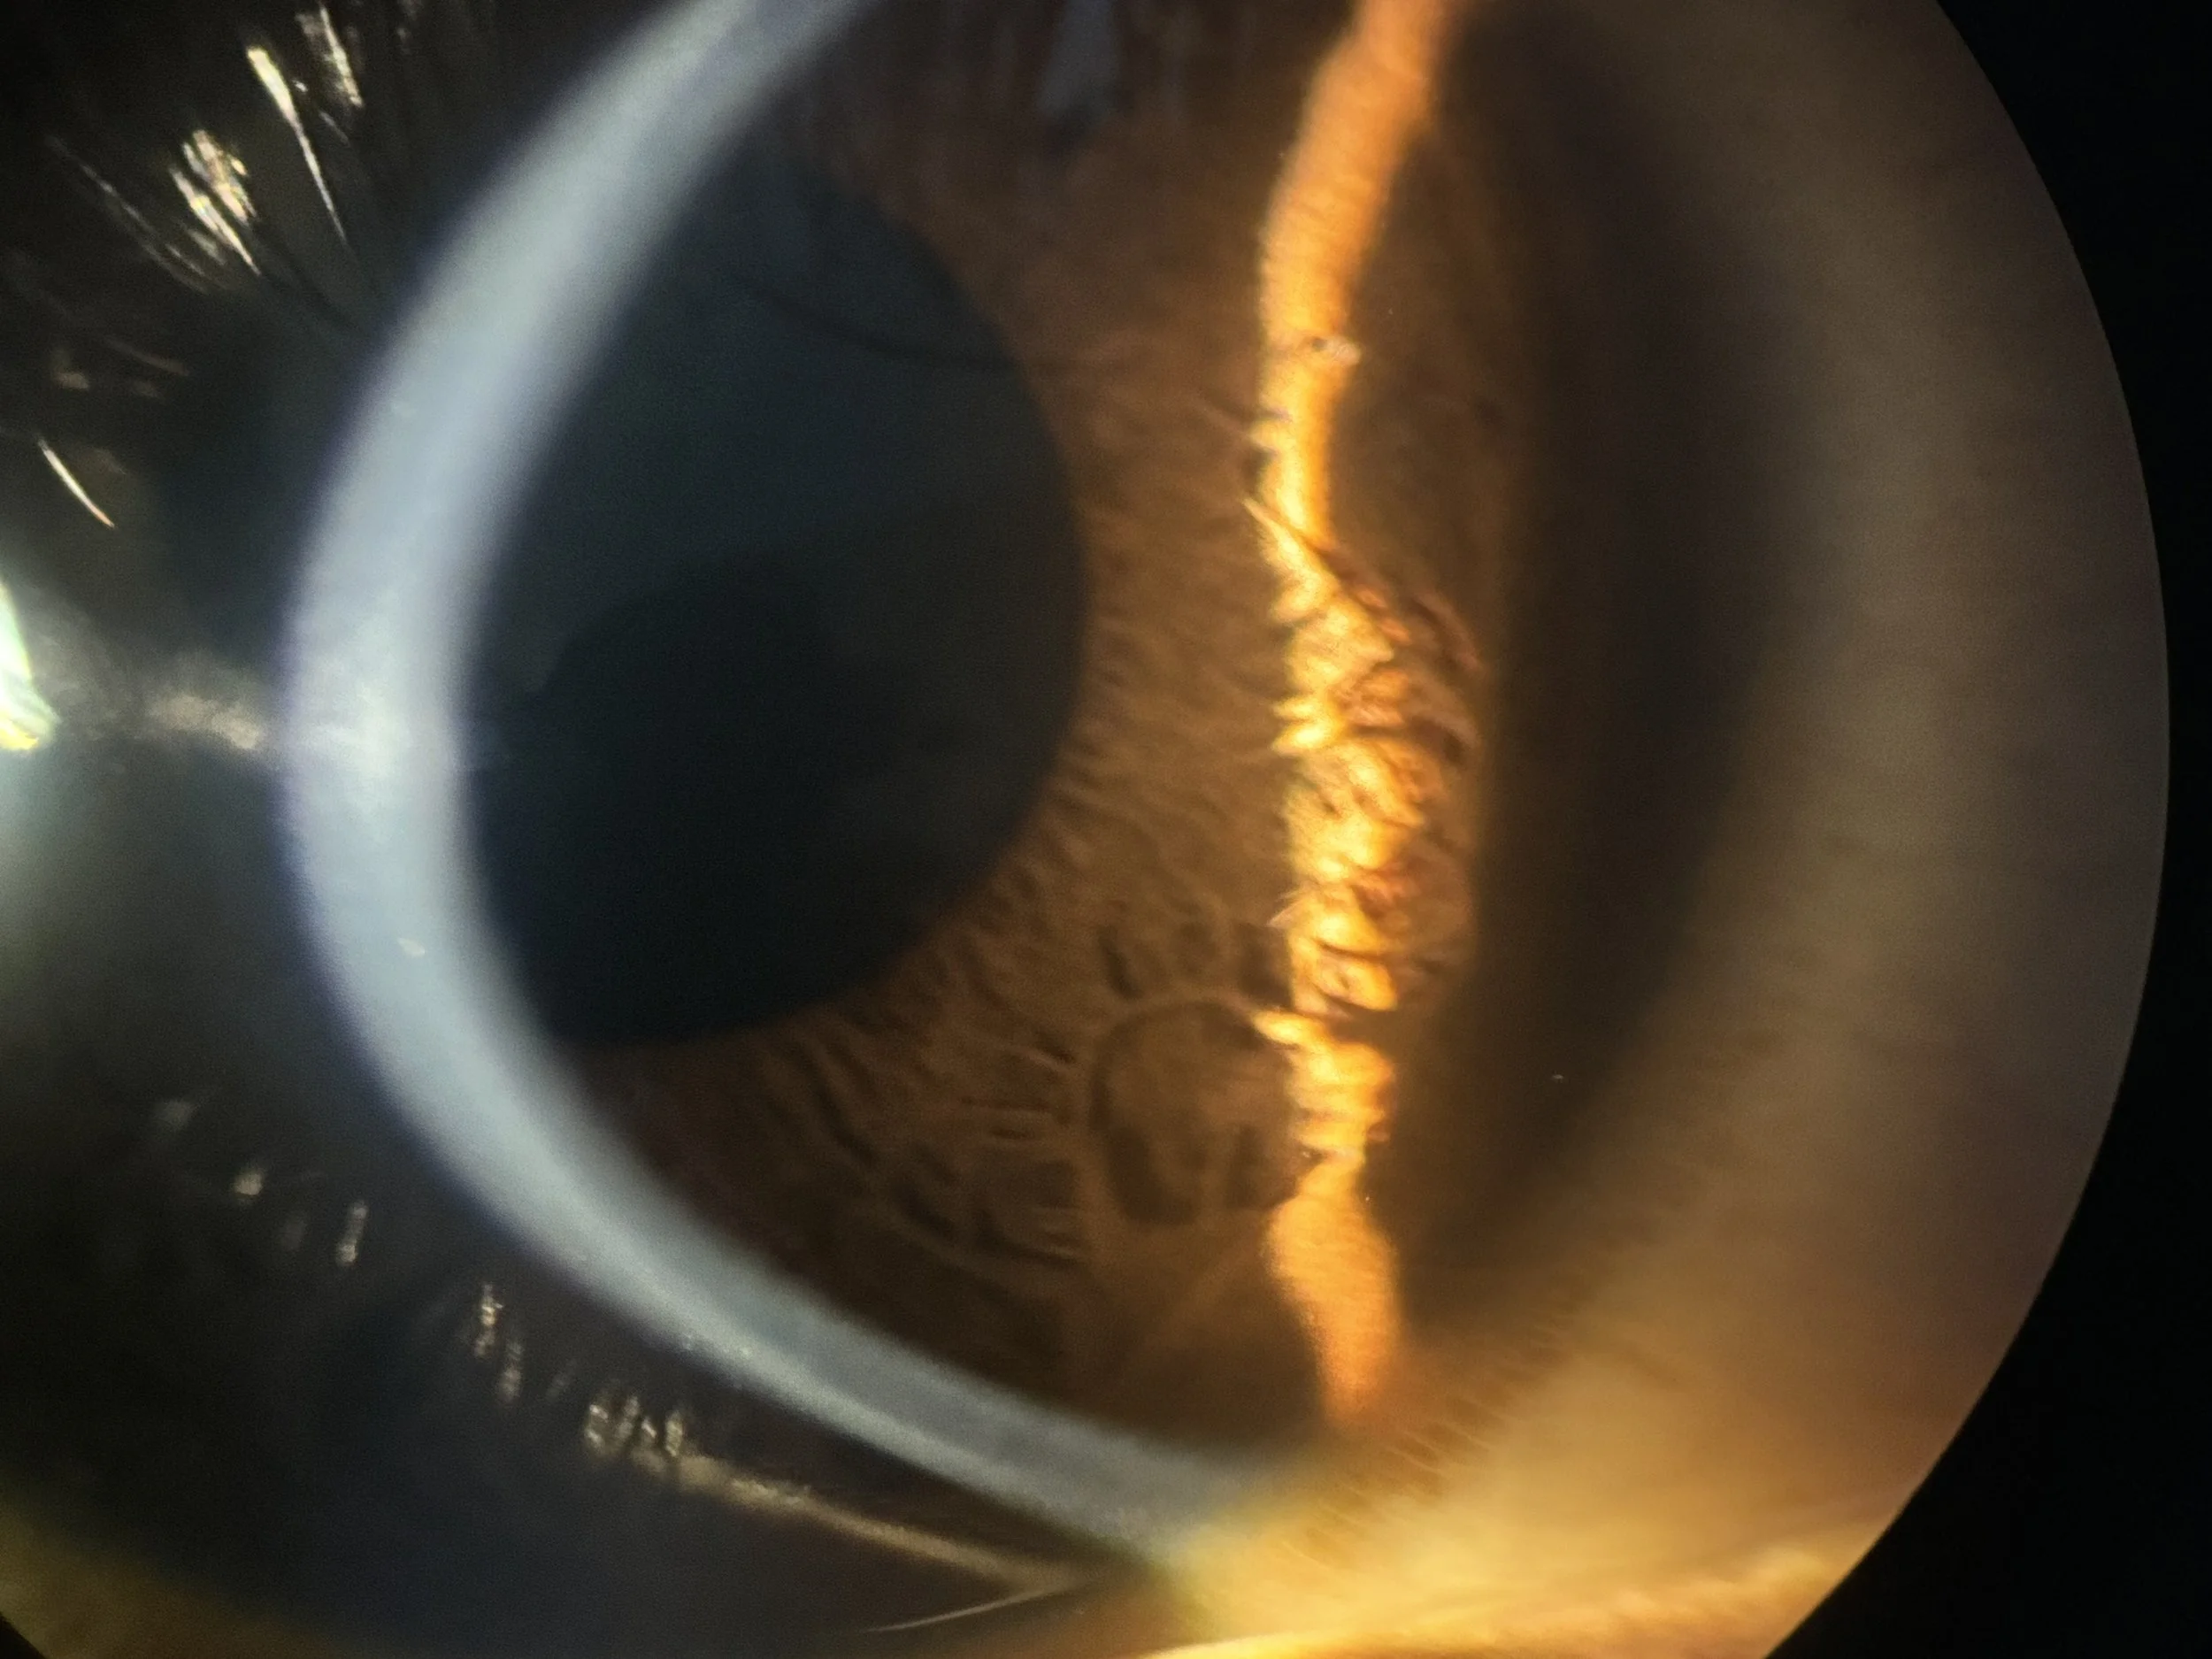

KERATOCONE